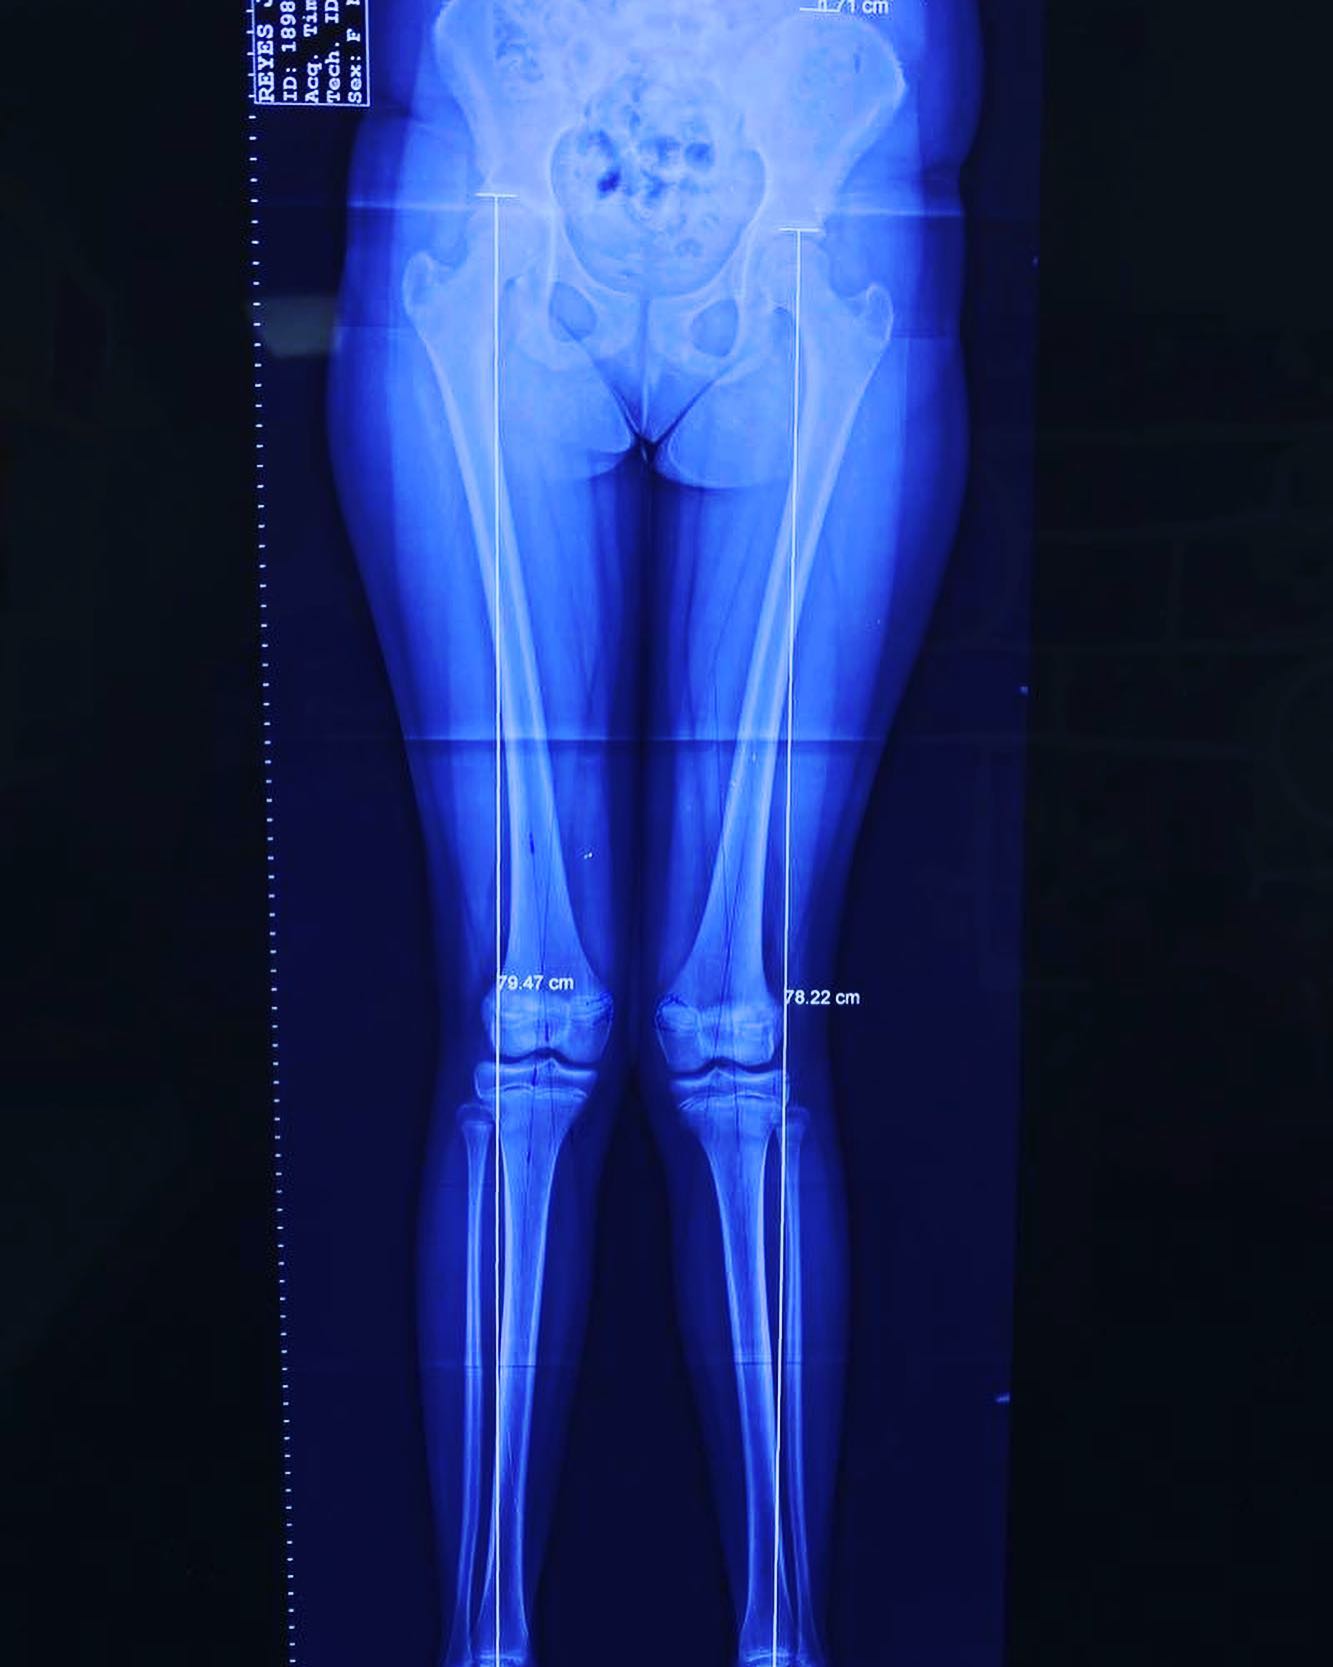

• Discrepancias de longitud en miembros pélvicos

También llamadas rodillas valgas o rodillas en varo, estas condiciones se refieren a la alineación de las piernas. Estas alineaciones pueden ser un estado natural del desarrollo de un niño o una niña hasta los 7 años de edad. Después de esta edad, ya no se consideran normales. Sin embargo, en algunos casos, esta deformidad puede aumentar hasta llegar a ser discapacitante y dolorosa, y es en ese momento cuando debe ser tratada.